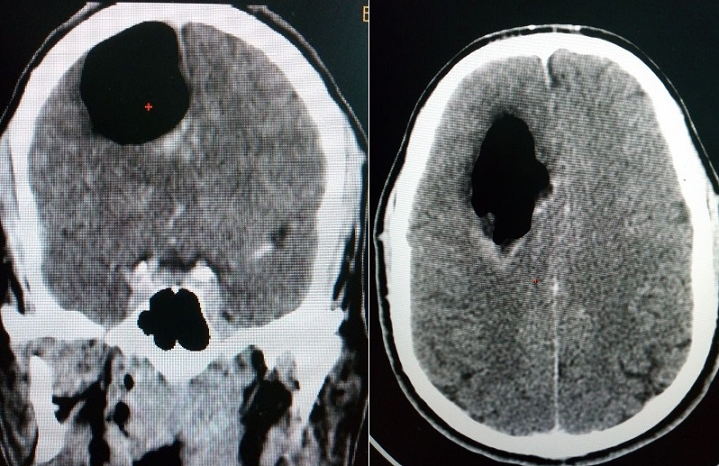

Il s´agit d´un patient de 34 ans, sans antécédents particuliers, admis aux urgences pour des troubles de conscience dans un contexte fébrile avec un important syndrome infectieux biologique. Le scanner cérébral met en évidence une volumineuse lésion aérique du centre semi-ovale droit (pneumocéphale), entourée d´un fin liseré œdémateux hypodense avec un léger effet de masse sur la ligne médiane et le parenchyme de voisinage. L´évolution a été marquée par l´aggravation de l´état et le décès du patient dans les 48 heures en milieu de réanimation pour défaillance multi-viscérale sur choc septique.